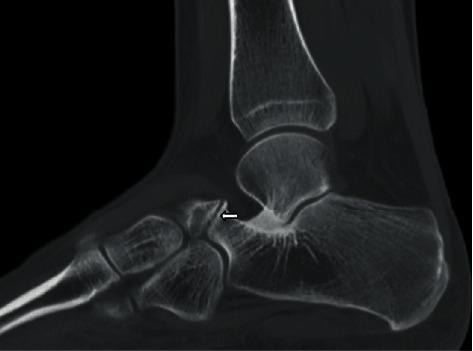

Coalition is defined as abnormal bridging between two bones, and the connection can be osseous or nonosseous. Most coalitions in the foot involve the hindfoot. Intermetatarsal coalition is thought to be much rarer than the more common hindfoot coalitions and has only been reported sporadically in the orthopedic literature. We present two patients with nonosseous intermetatarsal coalition presenting with nonspecific dorsolateral foot pain and describe the imaging findings of intermetatarsal coalition with different modalities. We suspect that whilst rarely described, intermetatarsal coalition is quite likely a more common underrecognized entity than a rare entity. This report is aimed at increasing the awareness of coalition in this location, in the radiology community, particularly the nonosseous ones, given that this condition can be debilitating but treatable.

联合被定义为两块骨头之间的异常连接,这种连接可以是骨性的或非骨性的。足部的大多数联合发生在后足。跖骨间联合被认为比更常见的后足联合要罕见得多,在骨科文献中仅有零星报道。我们报告了两名患有非骨性跖骨间联合且表现为足部背外侧非特异性疼痛的患者,并描述了不同影像学检查方式下跖骨间联合的表现。我们怀疑,虽然跖骨间联合很少被描述,但它很可能是一种比罕见病更常见却未被充分认识的病症。鉴于这种情况可能使人衰弱但可治疗,本报告旨在提高放射学界对该部位联合,尤其是非骨性联合的认识。